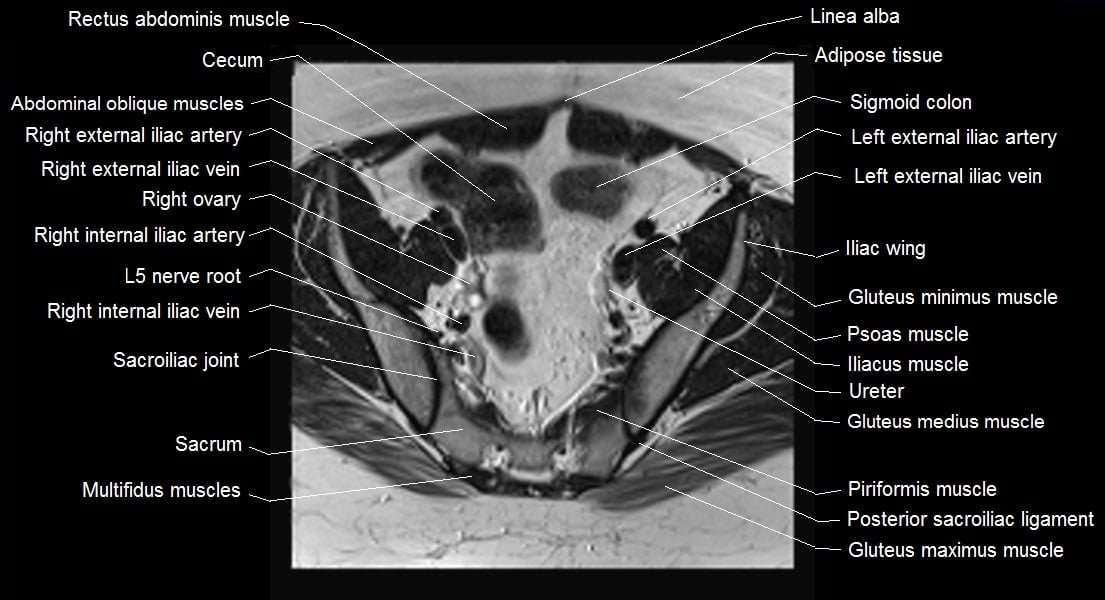

MRI Axial Cross-Sectional Anatomy of Female Pelvis

mri female pelvis anatomy axial